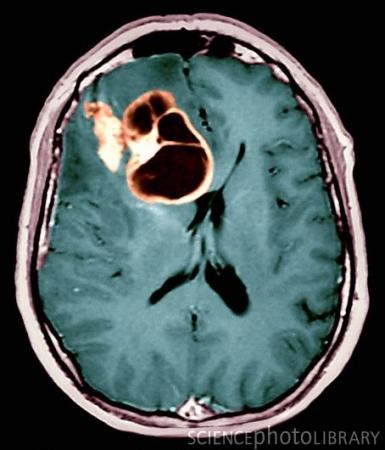

神经胶质瘤

新的疗法使用AdV-tk腺病毒载体,这一载体运输到癌细胞后,激活能杀死细胞的药物。同时这一疗法可激活对肿瘤的免疫应答。相关的研究发表在Clinical Oncology期刊网络版上。

研究人员称,这是首次对神经胶质瘤患者采用基因疗法和放射疗法。很多人关注这2种疗法对病人的毒理作用,然而事实上不存在这一情况。我们还不知道新疗法是否能提高病人的存活时间,但这一发现足够令人鼓舞了。